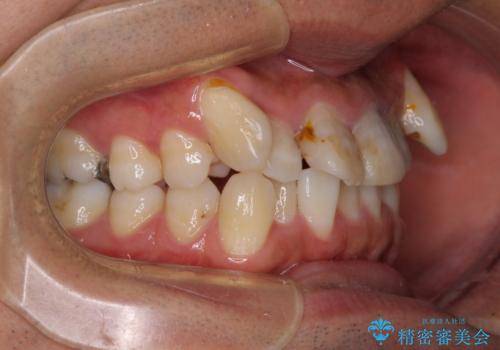

- 八重歯と上顎前歯の変色を気にして来院された患者様です。

上下ともに八重歯が顕著であったため、上下左右の第一小臼歯4本を抜歯し、ワイヤー装置での抜歯矯正を行うこととしました。